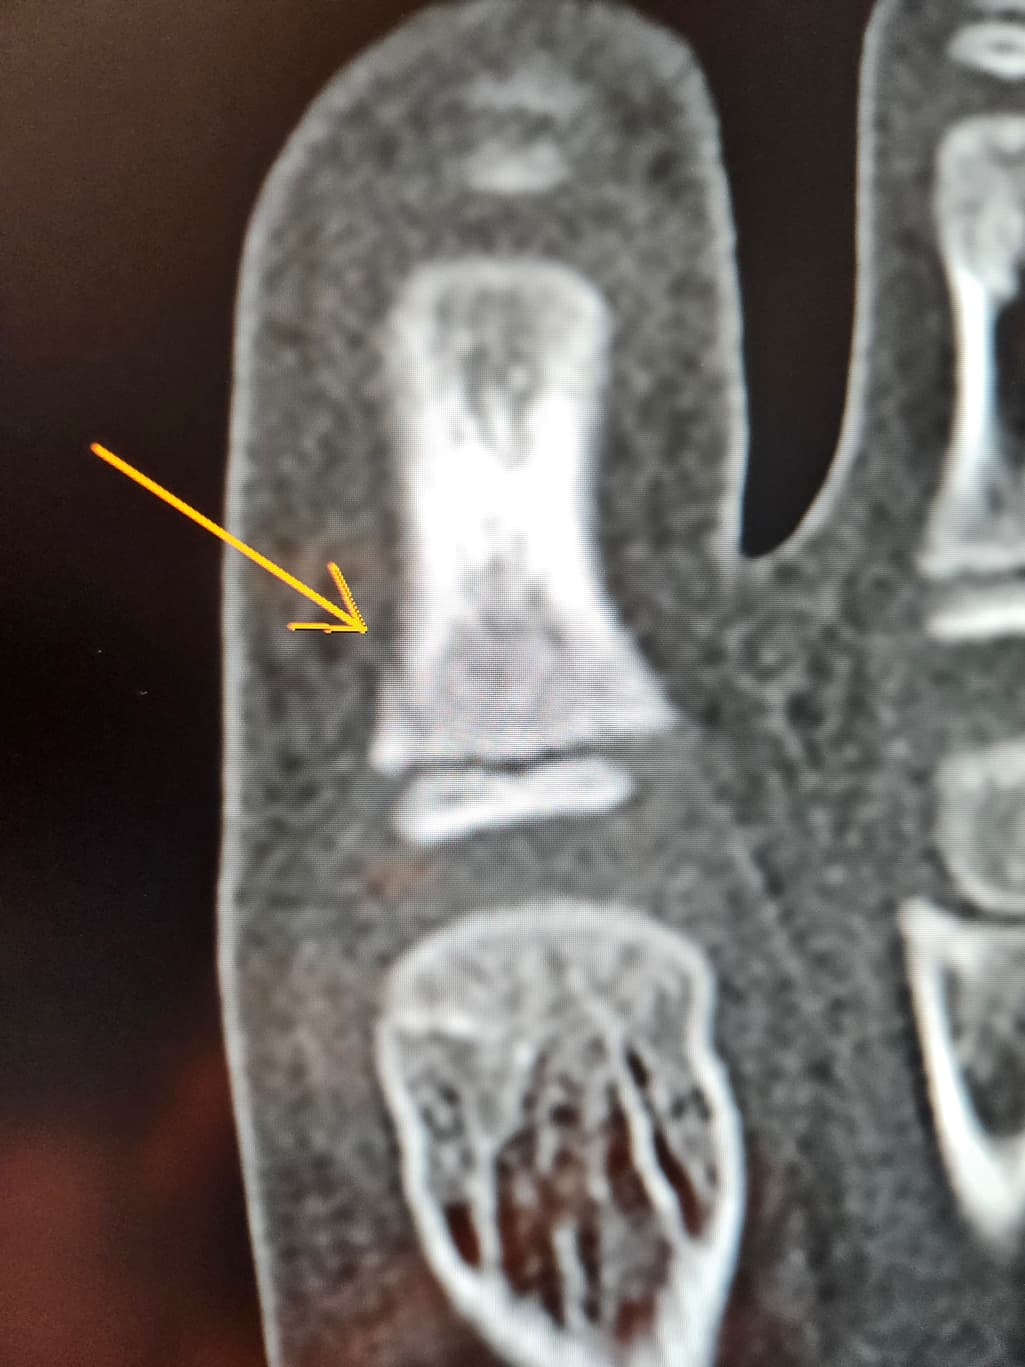

첫번째 사진은 엑스레이

8세남아 맨바닥에서 축구하다가 땅을 찼어요ㅠ